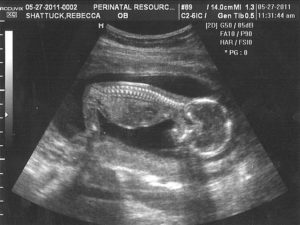

Современные технологии позволяют с почти 100%-ной вероятностью определить пол ребенка, начиная с 16 недели его развития. Узнать, кто же появится, будущим родителям и родственникам хочется как можно раньше. Поэтому многие используют приметы для новорожденных. Как определить вероятность рождения мальчика, девочки?

УЗИ является самым достоверным, популярным методом определения пола ребенка. Но так родителям придется ждать до 16-20 недели. Нередко малыш расположен спиной вперед, тогда врач УЗИ не может дать гарантий, мальчик это или будущая леди. Это остается загадкой до 9 месяца. Часто делают предположения благодаря размеру плода. Девочки чаще небольшие.

Помните! Бывают случаи, когда УЗИ не позволяет получить достоверный результат.

Помимо ультразвукового исследования есть медицинские, народные способы определения пола. Их используют с первых недель. Они не являются популярными из-за низкой вероятности, высокой стоимости.